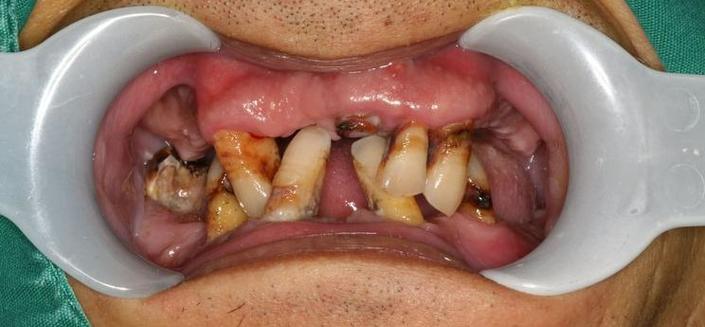

牙周支持组织破坏

牙齿的稳定性依赖牙周膜、牙槽骨和牙龈的健康,若患者正畸前存在未控制的牙周炎(如牙龈红肿、牙周袋深度>3mm、牙槽骨吸收),正畸力会进一步加剧牙周组织损伤,导致牙齿“过度松动”,正畸期间口腔卫生不良(如托槽周围食物残留、菌斑堆积)可能诱发牙龈炎、牙周炎,破坏牙周支持结构,引发松动。 -